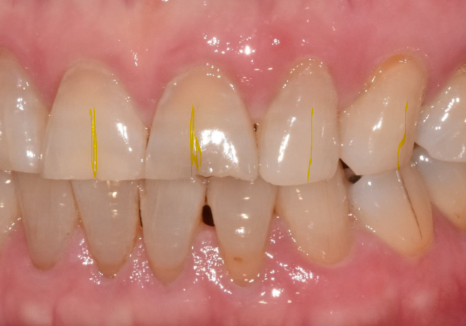

싱글 크라운을 선택한 결과

4개월 뒤,, 환자분께서 다시 내원하셨는데요.

식사 도중 앞니 하나(#11)가 부러져 오셨어요.

안타깝게도 뿌리만 남아

임플란트가 필요했습니다.

안타까운 상황이었지만,

다행히 하나씩 따로 씌워둔 덕분에

수습 과정은 훨씬 수월했습니다.^^

만약 6개를 하나로 묶어두었더라면

어땠을까요?

이 치아 하나 때문에 멀쩡한 나머지 5개까지

전부 뜯어내는 큰 공사가 됐을 텐데,

부러진 곳만 따로 수습하며

수월하게 치료를 마무리할 수 있었습니다.